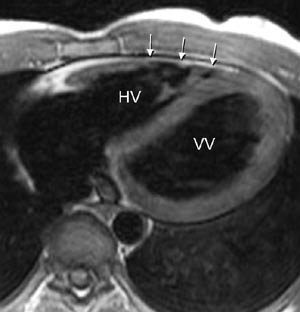

Perikardsykdom

MR er en god undersøkelse til å vise fokal eller generell fortykkelse av perikard og til å vise væske i perikard. Kalk i perikard vises imidlertid dårlig, til dette er CT betydelig bedre. MR er godt egnet for påvisning av konstriktiv perikarditt, og kan ved denne tilstand i tillegg til perikardfortykkelsen også vise dilatasjon av høyre atrium, v. cava inferior og levervenene, normalt stor eller liten høyre ventrikkel samt typiske kontraksjonsmønstre i venstre ventrikkel (16).